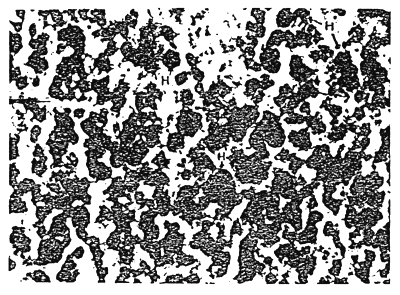

Observations on the deposition of haemosiderin pigments were made in Indian major carps, catla, rohu and mrigal and also in chinese silver carp under routine sampling for healthy monitoring programme. Insignificant amount of haemosiderin pigments were occasionally detected in healthy specimens of rohu, mrigal and silver carp in their liver, ovary and spleen sections. However, in healthy specimens of catla considerably high degree of haemosiderin deposition was observed especially in the ovary sections. Heavy deposition of haemosiderin pigment have been demonstrated in sections of ovary and liver of catla and in the liver sections of silver carp exhibiting the clinical symptoms of dropsy with signs of emaciation and anaemis. Histopathological observations revealed that the liver sections of diseased catla and silver carp with symptoms of dropsy and also the ovary sections of the healthy specimen of catla were showing heavy deposition of some pigment which was not found in the said sections of rohu and mrigal under H.E. stain. This pro pted us to ascertain the exact nature of these pigment deposition Perl's prussi n blue stain was used for confirming the presence of haemosiderin pigments which showed intensive positive reaction by taking dark blue colour. In the ovary sections the haemosiderin pigments were found to be deposited in between the oocytes in the interstitial spaces as shown in fig. I. This profuse accumulation of pigments in the terstitial spaces in the ovary might be the result of rupture of some of the blood vessels supplying the area thereby interferring with the normal growth of the ovarian cells. The excessive deposition of haemosiderin pigments in the ovary of catla possibly may have relevance with the poor maturity condition of catla in reservoir I or the farm where the response to hypophysation by catla breeders was found to be very poor. The testes of both healthy and sick specimens of catla did not show the presence of haemosiderin pigments.

Figure I. Photomicrograph of the ovary section of catla suffering from dropsy showing deposition of Hoemosiderin (H) pigment under perl's prussian blue stain.